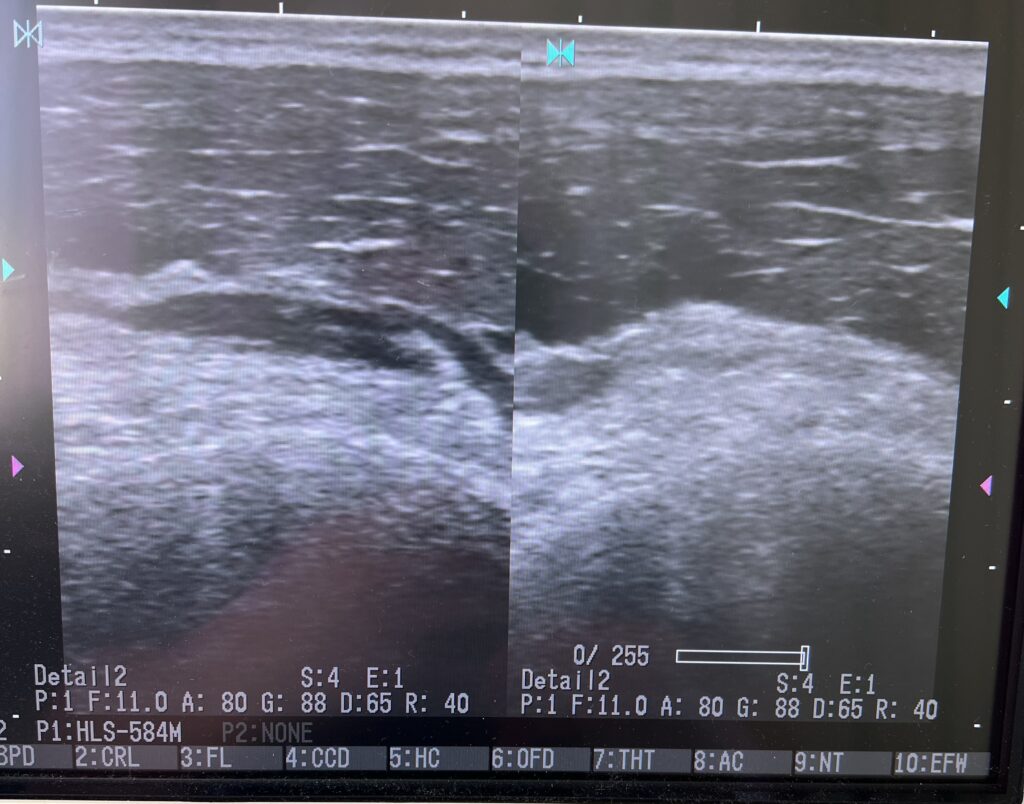

写真はサッカーの試合で接触転倒により膝を痛めて来院された患者様です。

今回のように **膝蓋上嚢血腫(しつがいじょうのうけっしゅ)**

を伴うケースでは、 膝の上部に腫れや熱感、水が溜まったような違和感が出現します。